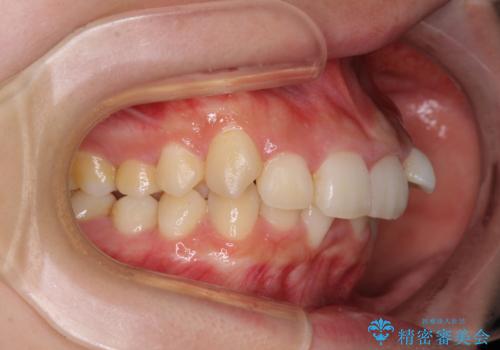

下顎前歯が隠れて突出した口元 ワイヤー装置での抜歯矯正

下顎骨の左右差や、上顎骨の前方位などが認められたため、上下左右の第1小臼歯4本を抜歯し、ワイヤー装置にて矯正治療を行うこととしました。

骨格的な左右差がありましたが、何とか当初予定していた期間で、左右対称の咬み合わせに仕上げることができました。